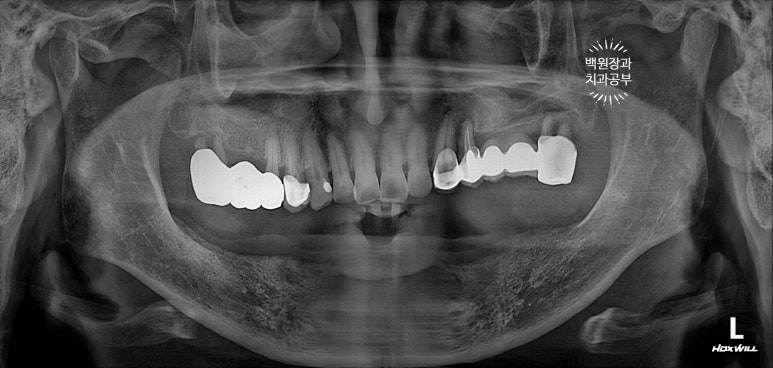

처음 내원하셨을 때 치과용 파노라마 소견입니다.

아래는 이가 하나도 없어 얼마 전 다른 치과에서 제작한 전체틀니를 사용하고 계셨고,

위 어금니는 브릿지로 되어있는데 만성치주염으로 흔들거리는 상황이었습니다.